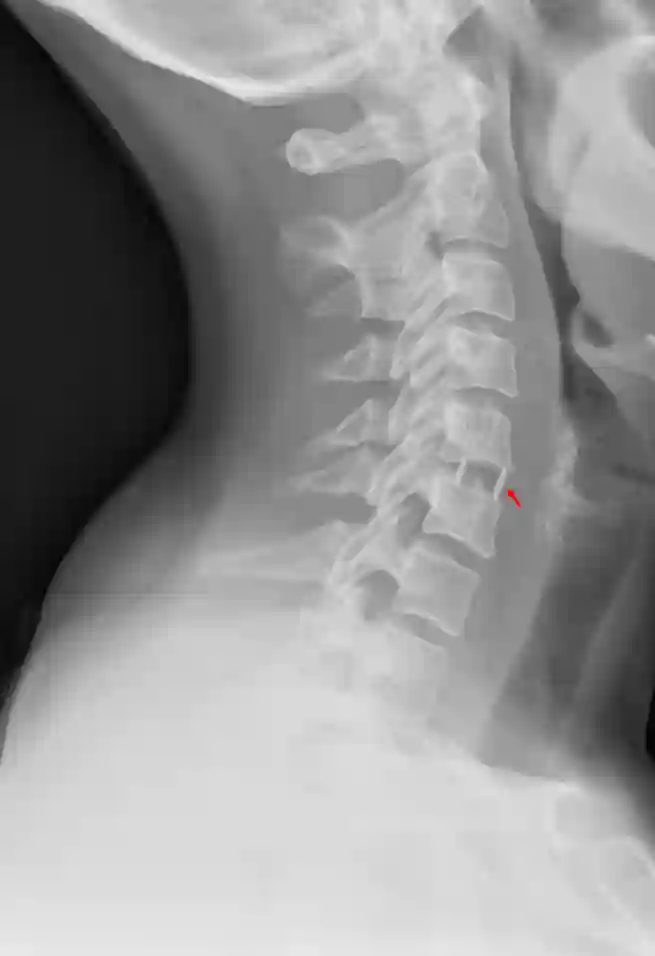

In manchen Fällen ist das zusätzliche Anbringen einer Platte sinnvoll oder auch notwendig. Beim Anbringen einer Platte sollte darauf geachtet werden, dass die Platte nicht mehr als 50 % der letzten von der Platte betroffenen Wirbelkörper abdeckt, um Anschlussosteophyten zu vermeiden[^3]

Bildgebung